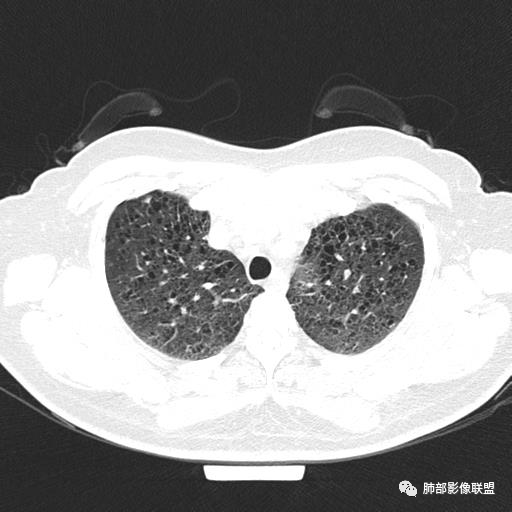

中年女性,不吸烟

双肺弥漫囊腔,累及肋膈角,囊腔形态相对规则单一。

符合LAM

CT平扫示双肺弥漫分布大小不等囊状薄壁透光区,无内、中、外带分布差异,间质稍示增厚。拟LAM

中年女性育龄期妇女,咳嗽气喘,无吸烟史,有苯吸入史。影像:双肺弥漫均匀小囊腔,无明显分布优势,囊腔形态欠规则,壁薄,部分囊腔边缘血管征,伴双肺弥漫磨玻璃影,无结节,考虑lam,鉴别苯中毒肺损伤,囊腔多有分布优势,小叶中心分布为主,形态规整等

女,46,活动性气喘1年。苯吸入史半年。胸部CT:两肺弥漫囊腔,上至肺尖,下至肋膈角,形态类似小囊腔。考虑:LAM,鉴别LIP,BHD,PLCH等。

双肺弥漫大小不一薄壁含气囊腔,囊间肺组织正常,正常肺背景,肺尖肺底受累;青年女性,气喘,支持LAM

CT表现:双肺弥漫大小不等的薄壁囊腔,囊壁<2mm,外形规则,血管影多位于囊腔周围,囊腔之间肺组织正常,随着疾病进展到晚期,囊腔变大、增多,不可胜数,囊腔可融合成较大的囊,与肺气肿相似,形成间质性肺纤维化。部分病例可出现结节影。